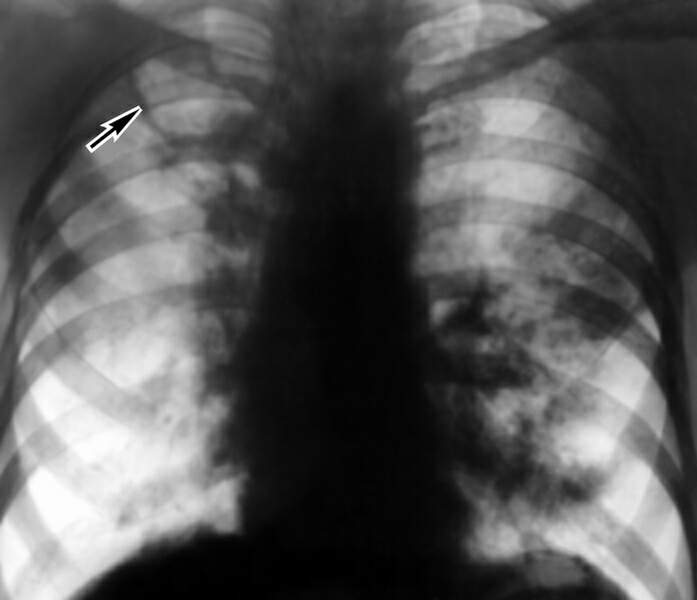

Однако наиболее доступным методом диагностики легочного туберкулеза является рентгенологическое обследование, которое возможно провести в форме рентгенографии, рентгеноскопии, томографии или флюорографии.

Первичная выявляемость тубркулеза осуществляется при помощи массовой флюорографии, проводимой в поликлиниках минимум 1 раз в год. Особую опасность представляет так называемый «декретированный контингент» - работники пищевой промышленности, медицинские сотрудники и т.д. Повышенный риск заболевания наблюдается у больных сахарным диабетом, пациенты, получающие иммунносупрессанты (глюкокортикоиды и цитостатики). При обнаружении патологических изменений в легких при флюорограмме, пациента следует отправить на дальнейшее обследование в условиях тубдиспансера. Программа массового флюорографического обследования в нашей стране позволила повысить выявляемость туберкулеза уже на ранних стадиях заболевания. Рентгенография органов грудной полости позволяет уточнить диагноз и определить локализацию и форму при наличии туберкулезного процесса. Патологические элементы могут иметь различную форму, расположение, размеры. Нередко выявляются явления пневмофиброза, бронхоэктазов и эмфиземы легких. Обнаружение кальцинированных очагов указывает на неактивный или перенесенный в анамнезе туберкулезный процесс. Уточнить данные позволит проведение томографии и МРТ.